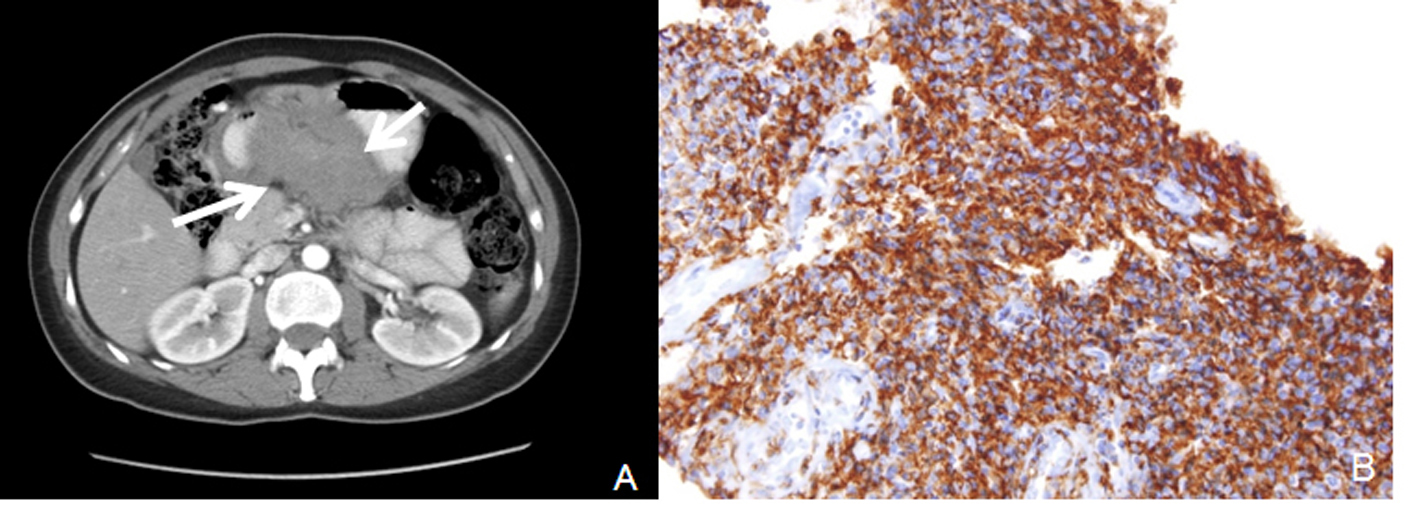

A 3 - 4 cm ulcerated polypoid mass in antrum and polypoid lesion with an impression of submucosal localization over the distal corpus (Fig. 1) were found in endoscopy in a female patient complaining of dyspeptic problems with an age of 54. Endoscopic biopsies revealed chronic inflammation and H.pylori was negative. First, abdominal tomography and then endoscopic ultrasonography were performed. Abdominal tomography showed a polypoid mass in the antrum with a diameter of 6 cm (Fig. 2A). Endoscopic ultrasonography yielded 5 - 6 cm transmural mass with serosal infiltration and heterogenous echogenity. Fine-needle aspiration biopsies were performed two times with a nondiagnostic material. Trucut biopsy was performed after cytologic examination yielding sample rich in lymphoid tissue. Histologic examination was reported as extranodal marginal-zone B-cell lymphoma with CD20 antigen (+) (Fig. 2B). The patient was consulted to Oncology Service for chemotherapy.

![]() Click for large image | Figure 2. A: Computerized tomography revealed antral mass; B: CD 20 positivity by immunohistochemical study in lymphoma cells. |